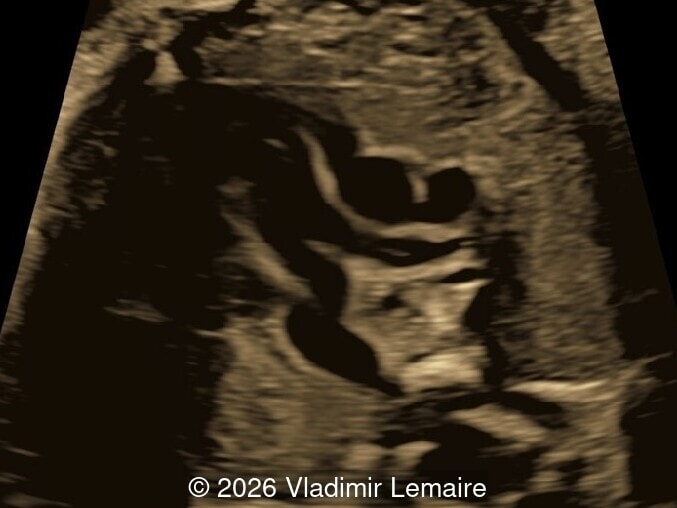

Axial plane of the fetal chest at the level of the four-chamber view.

Image 2 Axial plane of the fetal chest at the level of the four-chamber view.